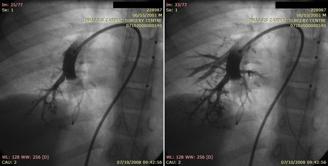

Pulmonary arteriovenous malformations and hereditary hemorrhagic telangiectasia (Rendu- Osler- Weber syndrome)

Gketsi Vasiliki, Kyrochristou Electra, Vlachou Georgia, Tsoutsinos Alexandros, Apostolopoulou Soteria

AVP= Amplatzer vascular plugs

Rendu-Osler-Weber.